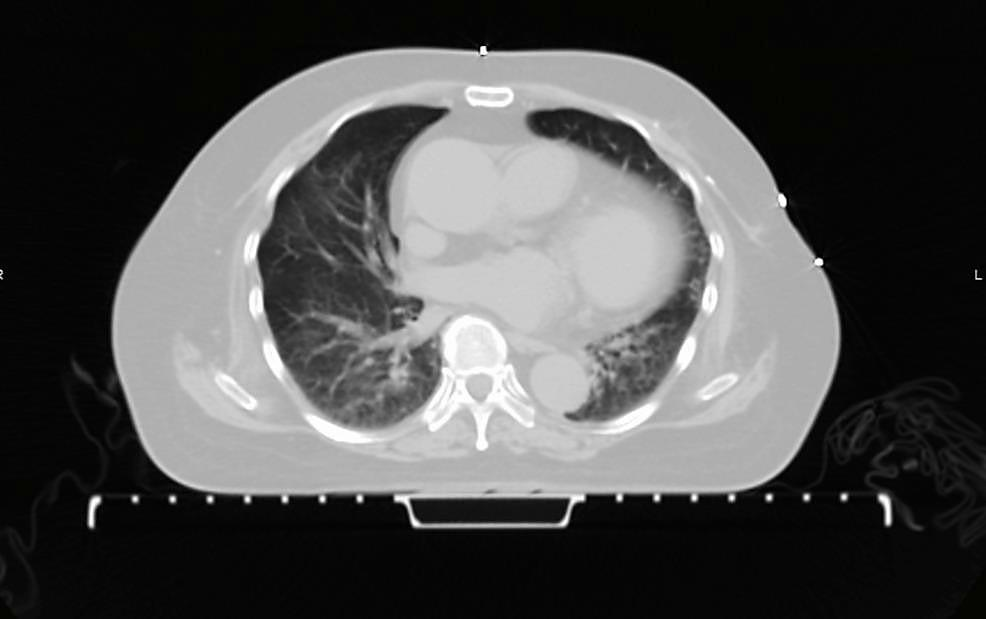

急诊科动脉血气分析显示1型呼吸衰竭。血液检查显示白细胞(WBC)计数正常,为6.3×10⁹/L,C反应蛋白(CRP)升高至99.8mg/dL。门诊就诊时的胸片未见明显异常。急诊科复查胸片显示双侧弥漫性网状阴影。呼吸道病原体检测(病毒PCR)显示人鼻病毒/肠道病毒和流感嗜血杆菌感染。痰培养及药敏(2023年10月16日)显示鲍曼不动杆菌生长,对氨苄西林-舒巴坦、头孢他啶和头孢吡肟敏感。其他检查包括结核(TB)相关检查、TB GeneXpert、血培养均无阳性结果。由于抗生素治疗1周后仍无改善,最终进行了CT肺动脉造影(CTPA),显示右上叶前段和后段以及左下叶后段的亚段肺栓塞,并伴有双侧感染性肺部改变,包括磨玻璃影和实变影(图1)。

图1. 胸部CT显示双肺中央支气管血管周围分布的磨玻璃影及网状肺改变